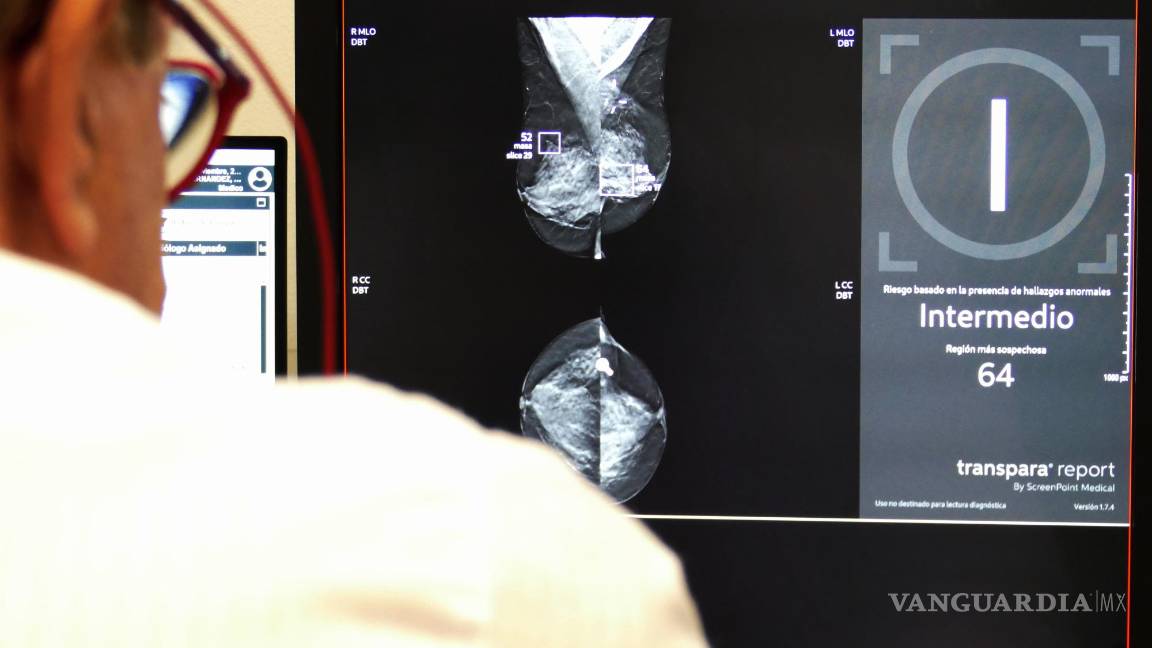

$!Imagen de la estadificación de riesgo de una mamografía a través de IA (mensaje a la derecha), en esta se marca la masa sospechosa encuadradas en violeta.

Explica que “en el análisis mamográfico, el programa de IA analiza mamografías y ecografías, detecta lesiones sospechosas y ofrece un índice de riesgo de cáncer”.

Estos análisis se realizan de forma automática. No evitan que el radiólogo deba seguir analizando la prueba, pero permiten que los más expertos puedan dedicarse solo a valorar las pruebas más complejas”, explica el doctor Martínez de Vega de Vega.

Estas IA se han entrenado analizando millones de imágenes en las que han estudiado muchas características, como microcalcificaciones, densidades asimétricas o márgenes especulados, clasifican toda esta información y nos ofrecen un análisis muy fiable”, destaca.